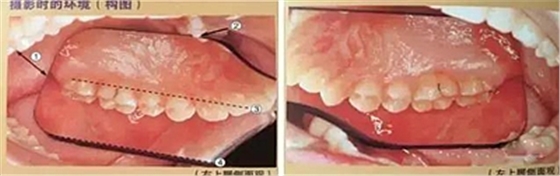

五、頰側(cè)面攝影

口腔攝影方法與技巧

①拿掉攝影側(cè)的口角拉鉤

②輕輕拉住非攝影側(cè)的口角拉鉤

③調(diào)整患者面部的方向(拍右側(cè)向右轉(zhuǎn),拍左側(cè)向左轉(zhuǎn))

④反光板遠離牙列

⑤牙列在反光板中央位置為好

⑥反光板邊緣與咬合平面平行

⑦反光板開口角度盡可能大

六、咬合面的拍攝